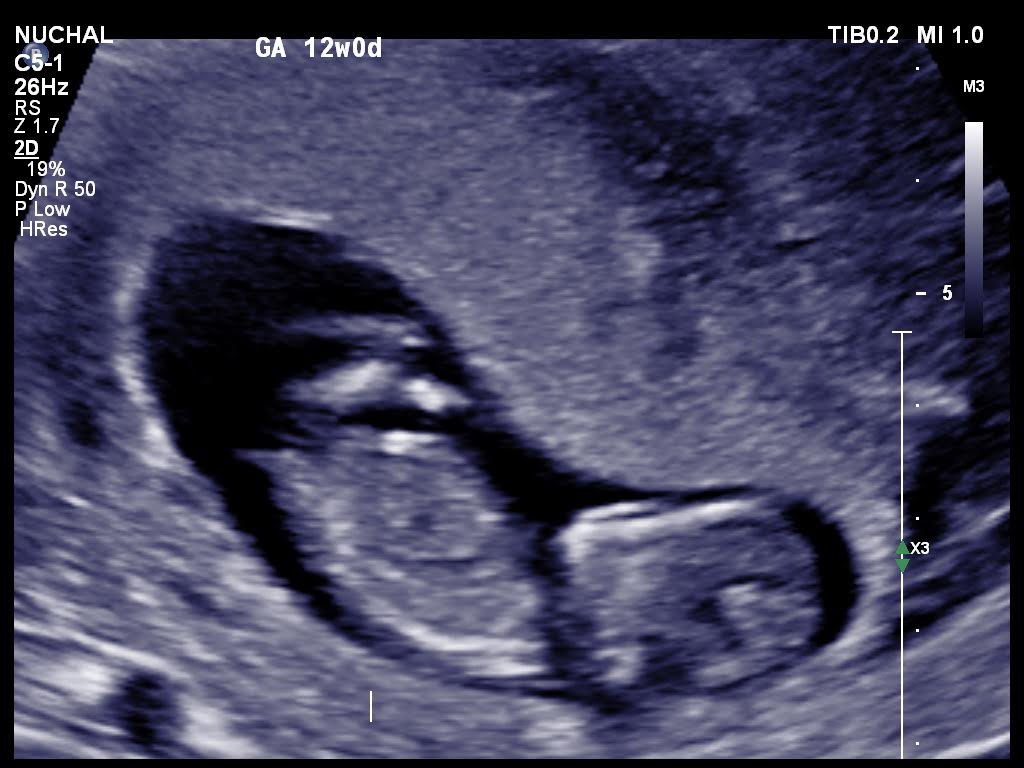

Is it possible for anybody to suggest the gender please from these 12 weeks ultrasound scans.